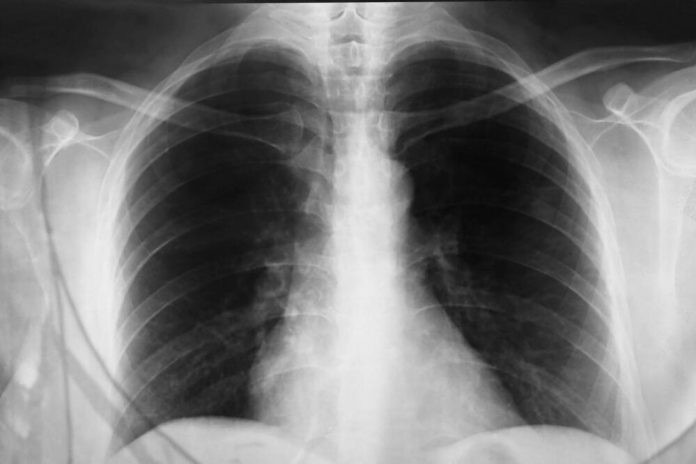

Dijagnoza se postavlja na osnovu kliničke slike, pregleda pluća i rendgen snimka, a ponekad su potrebne laboratorijske i mikrobiološke analize kako bi se utvrdio tačan uzročnik. Lečenje zavisi od vrste infekcije – bakterijska pneumonija zahteva antibiotike, dok se virusna obično leči simptomatski, uz odmor, tečnost i lekove za snižavanje temperature. Kod težih oblika neophodna je hospitalizacija i terapija kiseonikom.